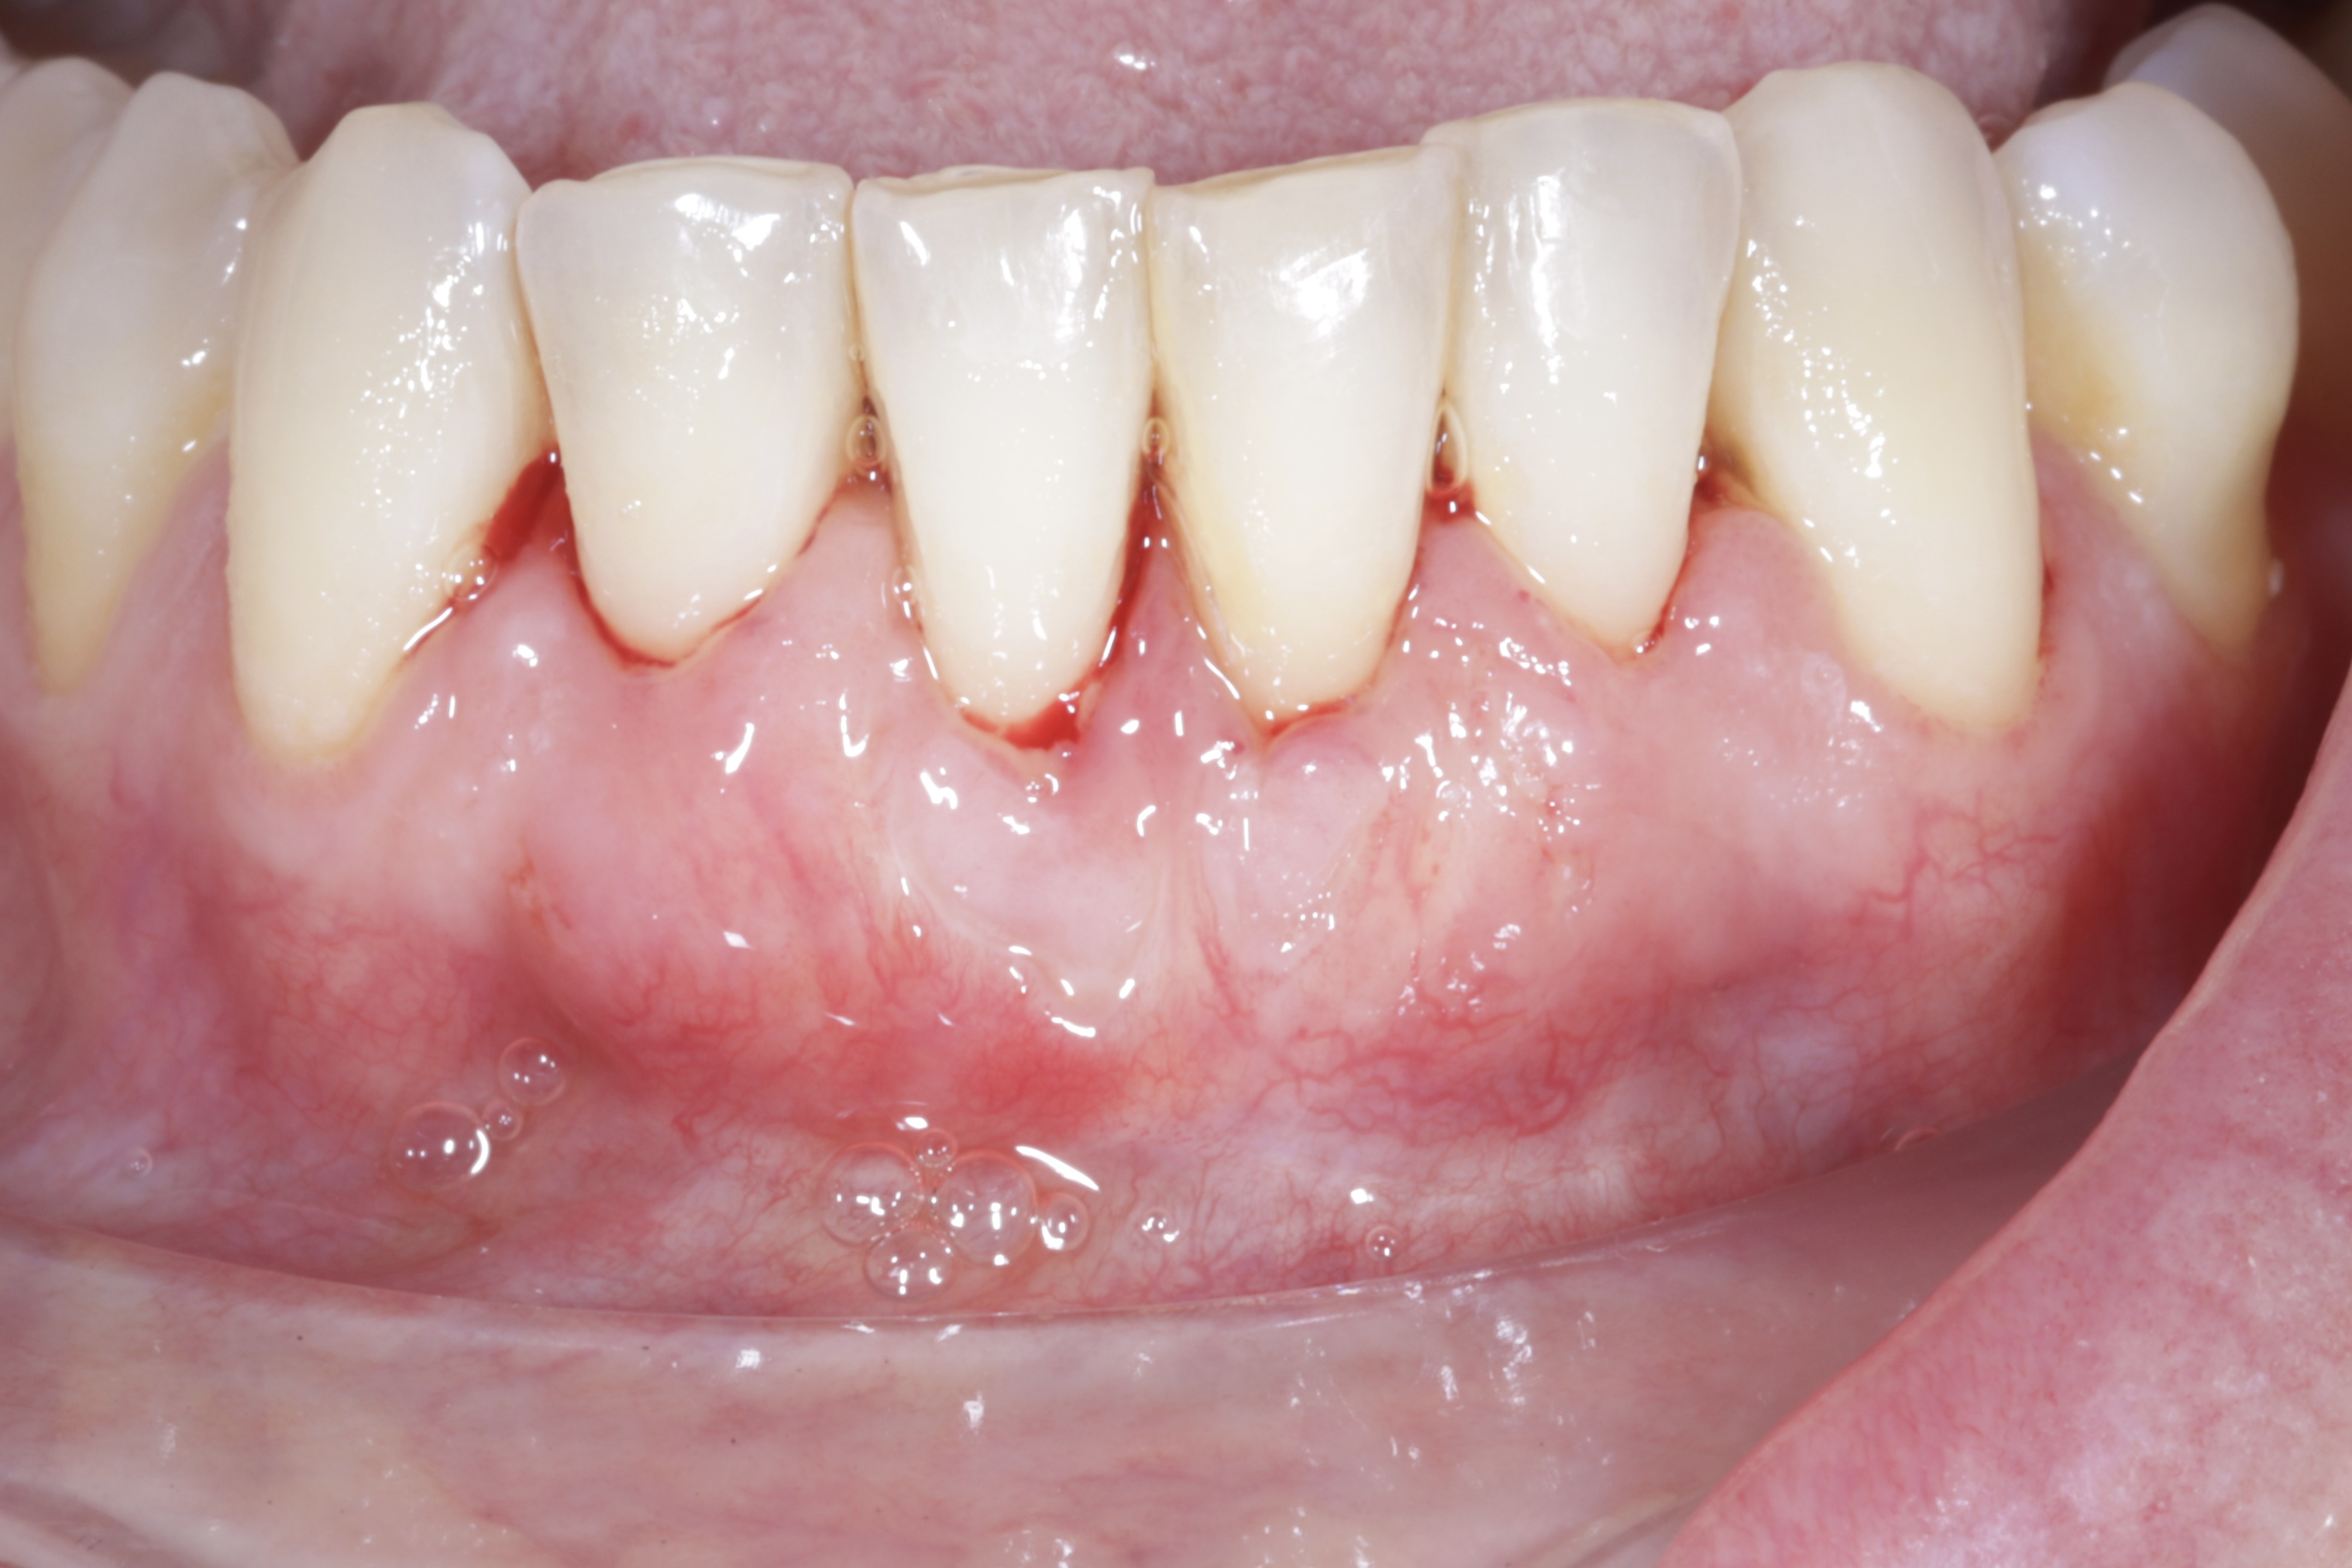

Durante una mañana, asistirás a una Cirugía Mucogingival de recubrimiento radicular de recesiones múltiples en IV y V sextante (36 a 43).

Aprende la planificación y técnica de la cirugía Mucogingival para el recubrimiento de recesiones y aumento de banda queratinizada en el sector anteroinferior

Una estancia clínica pensada para quienes quieran iniciarse o dar un paso más en el campo de la cirugía mucogingival. Durante esta experiencia tendrás la oportunidad de aprender en directo cómo se planifica y se lleva a cabo una cirugía mucogingival mediante técnica de Túnel.

Formación teórico-práctica completa sobre las técnicas más avanzadas en cirugía mucogingival. Durante dos días intensivos, los participantes aprenderán desde la evidencia científica y la anatomía de las zonas donantes hasta la ejecución de injertos, cubrimiento radicular y aumento de